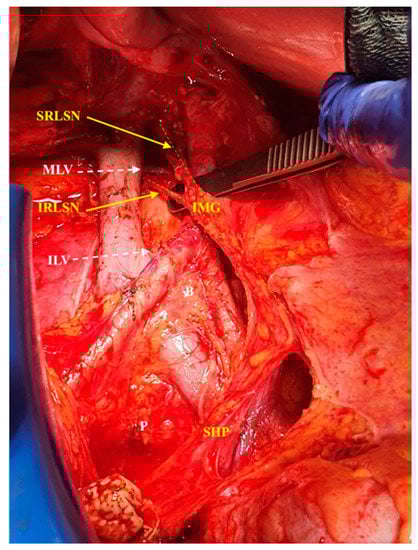

2.1. The Anatomy of Aortic Plexus

2.2. Dissection of the Right Cord of the Aortic Plexus

2.3. Dissection of the Left Cord of the Aortic Plexus